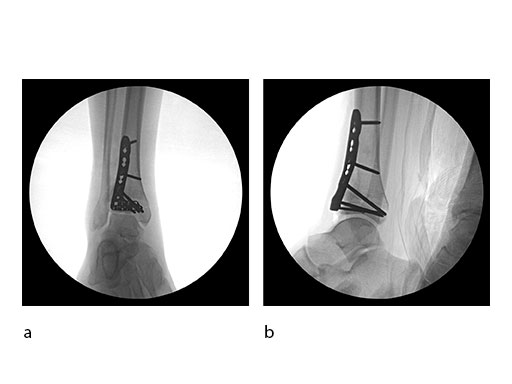

Surgeons performed an anterolateral surgical approach and distracted the joint using the distraction clamp and osteotome (Fig 2). The fracture was fixated with a VA-LCP Anterolateral Distal Tibia Plate (Fig 35).

Case 2: Scaffolding fall (Case provided by Mark Lee, Sacramento, USA)